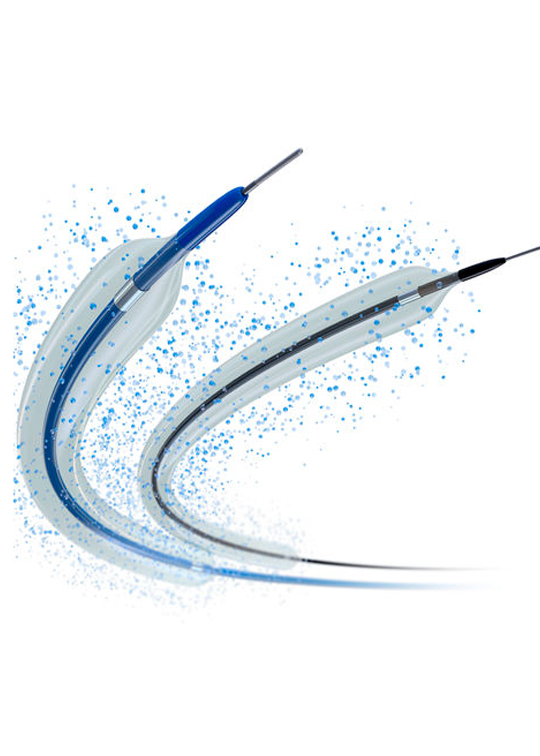

AREAS INVOLVED

Changyuan Precision Medical has a professional R&D team, robust control system design,

mature mechanical technology, versatile software platform, advanced R&D facilities,

and efficient electronic design, along with a dedicated R&D laboratory to ensure design

validation at every stage and product quality.